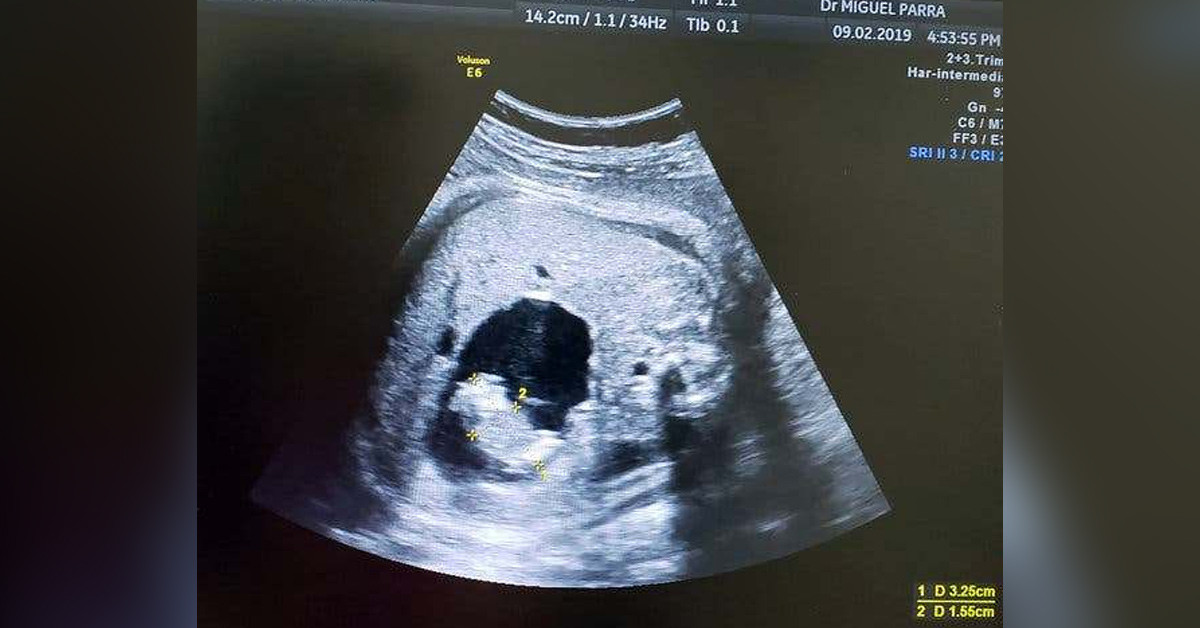

Kolombiya, Barranquilla’da yaşayan Monica Vega’nın hekimleri doğumdan iki ay evvel kontrol sırasında ultrasonda iki göbek kordonu olduğunu fark ettiler.

Fakat bu hal Vega ikiz bebeklere gebe olduğu için değildi. Vega’nın beklediği kız bebek rahimdeki öteki fetüsü emmiş ve ardından ona göbek kordonu ile bağlanmıştı

Bu yüzden de Vega’nın hekimleri, paraziter ikizin büyüyüp gelişmekte olan bebeğin organlarını yaralayabileceğinden endişelendikleri için Vega’yı anında ameliyata aldı.